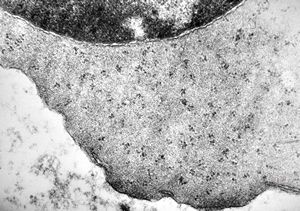

F,50y. | blood … lymphocyte and thrombocyte